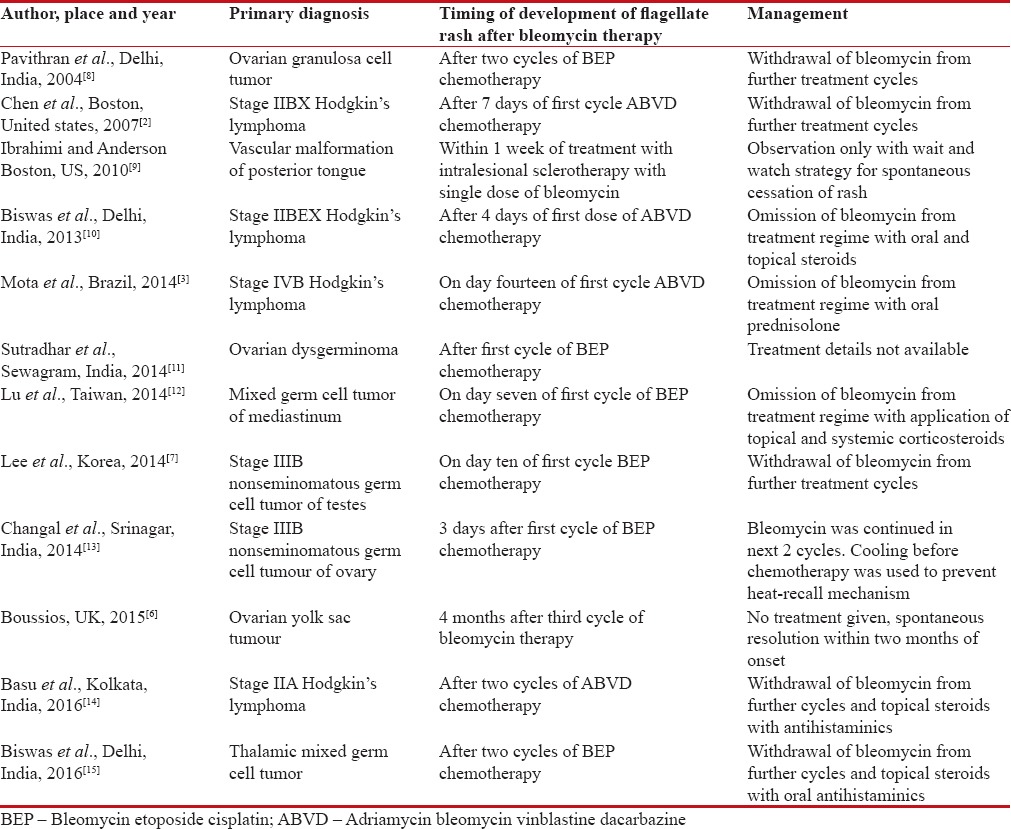

Bleomycin is an antineoplastic agent belonging to glycopeptides group and is inactivated by enzyme bleomycin hydrolase which is deficient in the skin and considerably less in concentration in the lungs leading to an increased cutaneous concentration of bleomycin in these tissues. The common mucocutaneous lesions described as a side effect of bleomycin therapy are pigmentation (~50%), alopecia (~50%), and flagellate dermatitis (8%–66%).[4] Flagellate erythema as a cutaneous manifestation of bleomycin therapy was first described in 1970.[6] The exact pathogenesis of bleomycin-induced flagellate dermatitis is still unknown and different other theories have been proposed for the same like micro-trauma, inflammatory oncotaxis, increased melanogenesis, heat recall, and reduced epidermal turnover allowing prolonged melanocytes – keratinocyte contact.[4] It is usually dose dependent and a reaction as a result of bleomycin irrespective of the route of administration or malignancy being treated and usually occurs after a cumulative dose of 90–285 mg, but some cases have been reported with doses as low as 15 mg given parenterally.[7,8] It follows the administration of bleomycin by a duration ranging from day 1 to 9 weeks and may persist for up to 6 months.[8] Previous reports have also described its occurrence even with a single dose of intralesional bleomycin used for sclerotherapy.[9] The course of bleomycin induced flagellate erythema is varied. The patient can be asymptomatic or may present with a prodrome of generalized pruritus within hours to weeks of bleomycin administration and the subsequent appearance of erythematous linear streaks which progress to typical flagellate hyperpigmentation.[7] Lesions lacks specific distribution and can occur anywhere over face, neck and trunk. Histopathologically, a spectrum of morphological findings can be seen on including urticarial hypersensitivity reaction, localized increase in melanogenesis from hyperactive and enlarged melanocytes, inflammatory oncotaxis, and lymphocytic vasculitis.[7] Salient features of different cases of bleomycin causing a flagellate rash with different doses, different routes of administration and management previously reported in the literature are summarized in Table 1.

Table 1

Previous reports of bleomycin causing flagellate rash with different doses, different routes of administration, and management reported in literature

|

Our patient noticed bleomycin-induced flagellate rash after 3 cycles of chemotherapy (total cumulative dose of 270 units) which was first noticed over the trunk and then gradually spread over other body parts. The lesion was pruritic in our patient also as were previously reported. There is no specific treatment, but avoidance of bleomycin leads to eventual clearance over months to years. However, re-exposure may produce an aggravated reaction. The patient has shown a good response to topical steroids and withdrawal of bleomycin from subsequent chemotherapy cycles.[15]